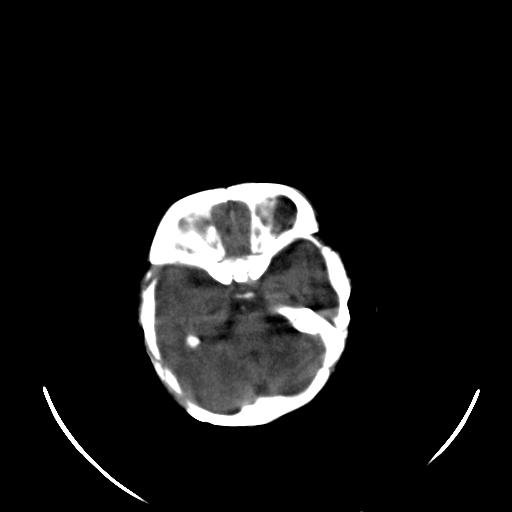

患儿 女性 1个月  今天发现阵发性抽搐  双眼上翻、凝视,嘴唇及面色青紫

双侧颞枕叶片状低密度影,考虑新生儿却血缺氧性脑病可能

左侧额叶见班片样低密度灶,症状像癫痫,可能与之有关。

新生儿却血缺氧性脑病不排除!

左侧额叶见班片样低密度灶,建议mr

考虑hie。

考虑新生儿hie。